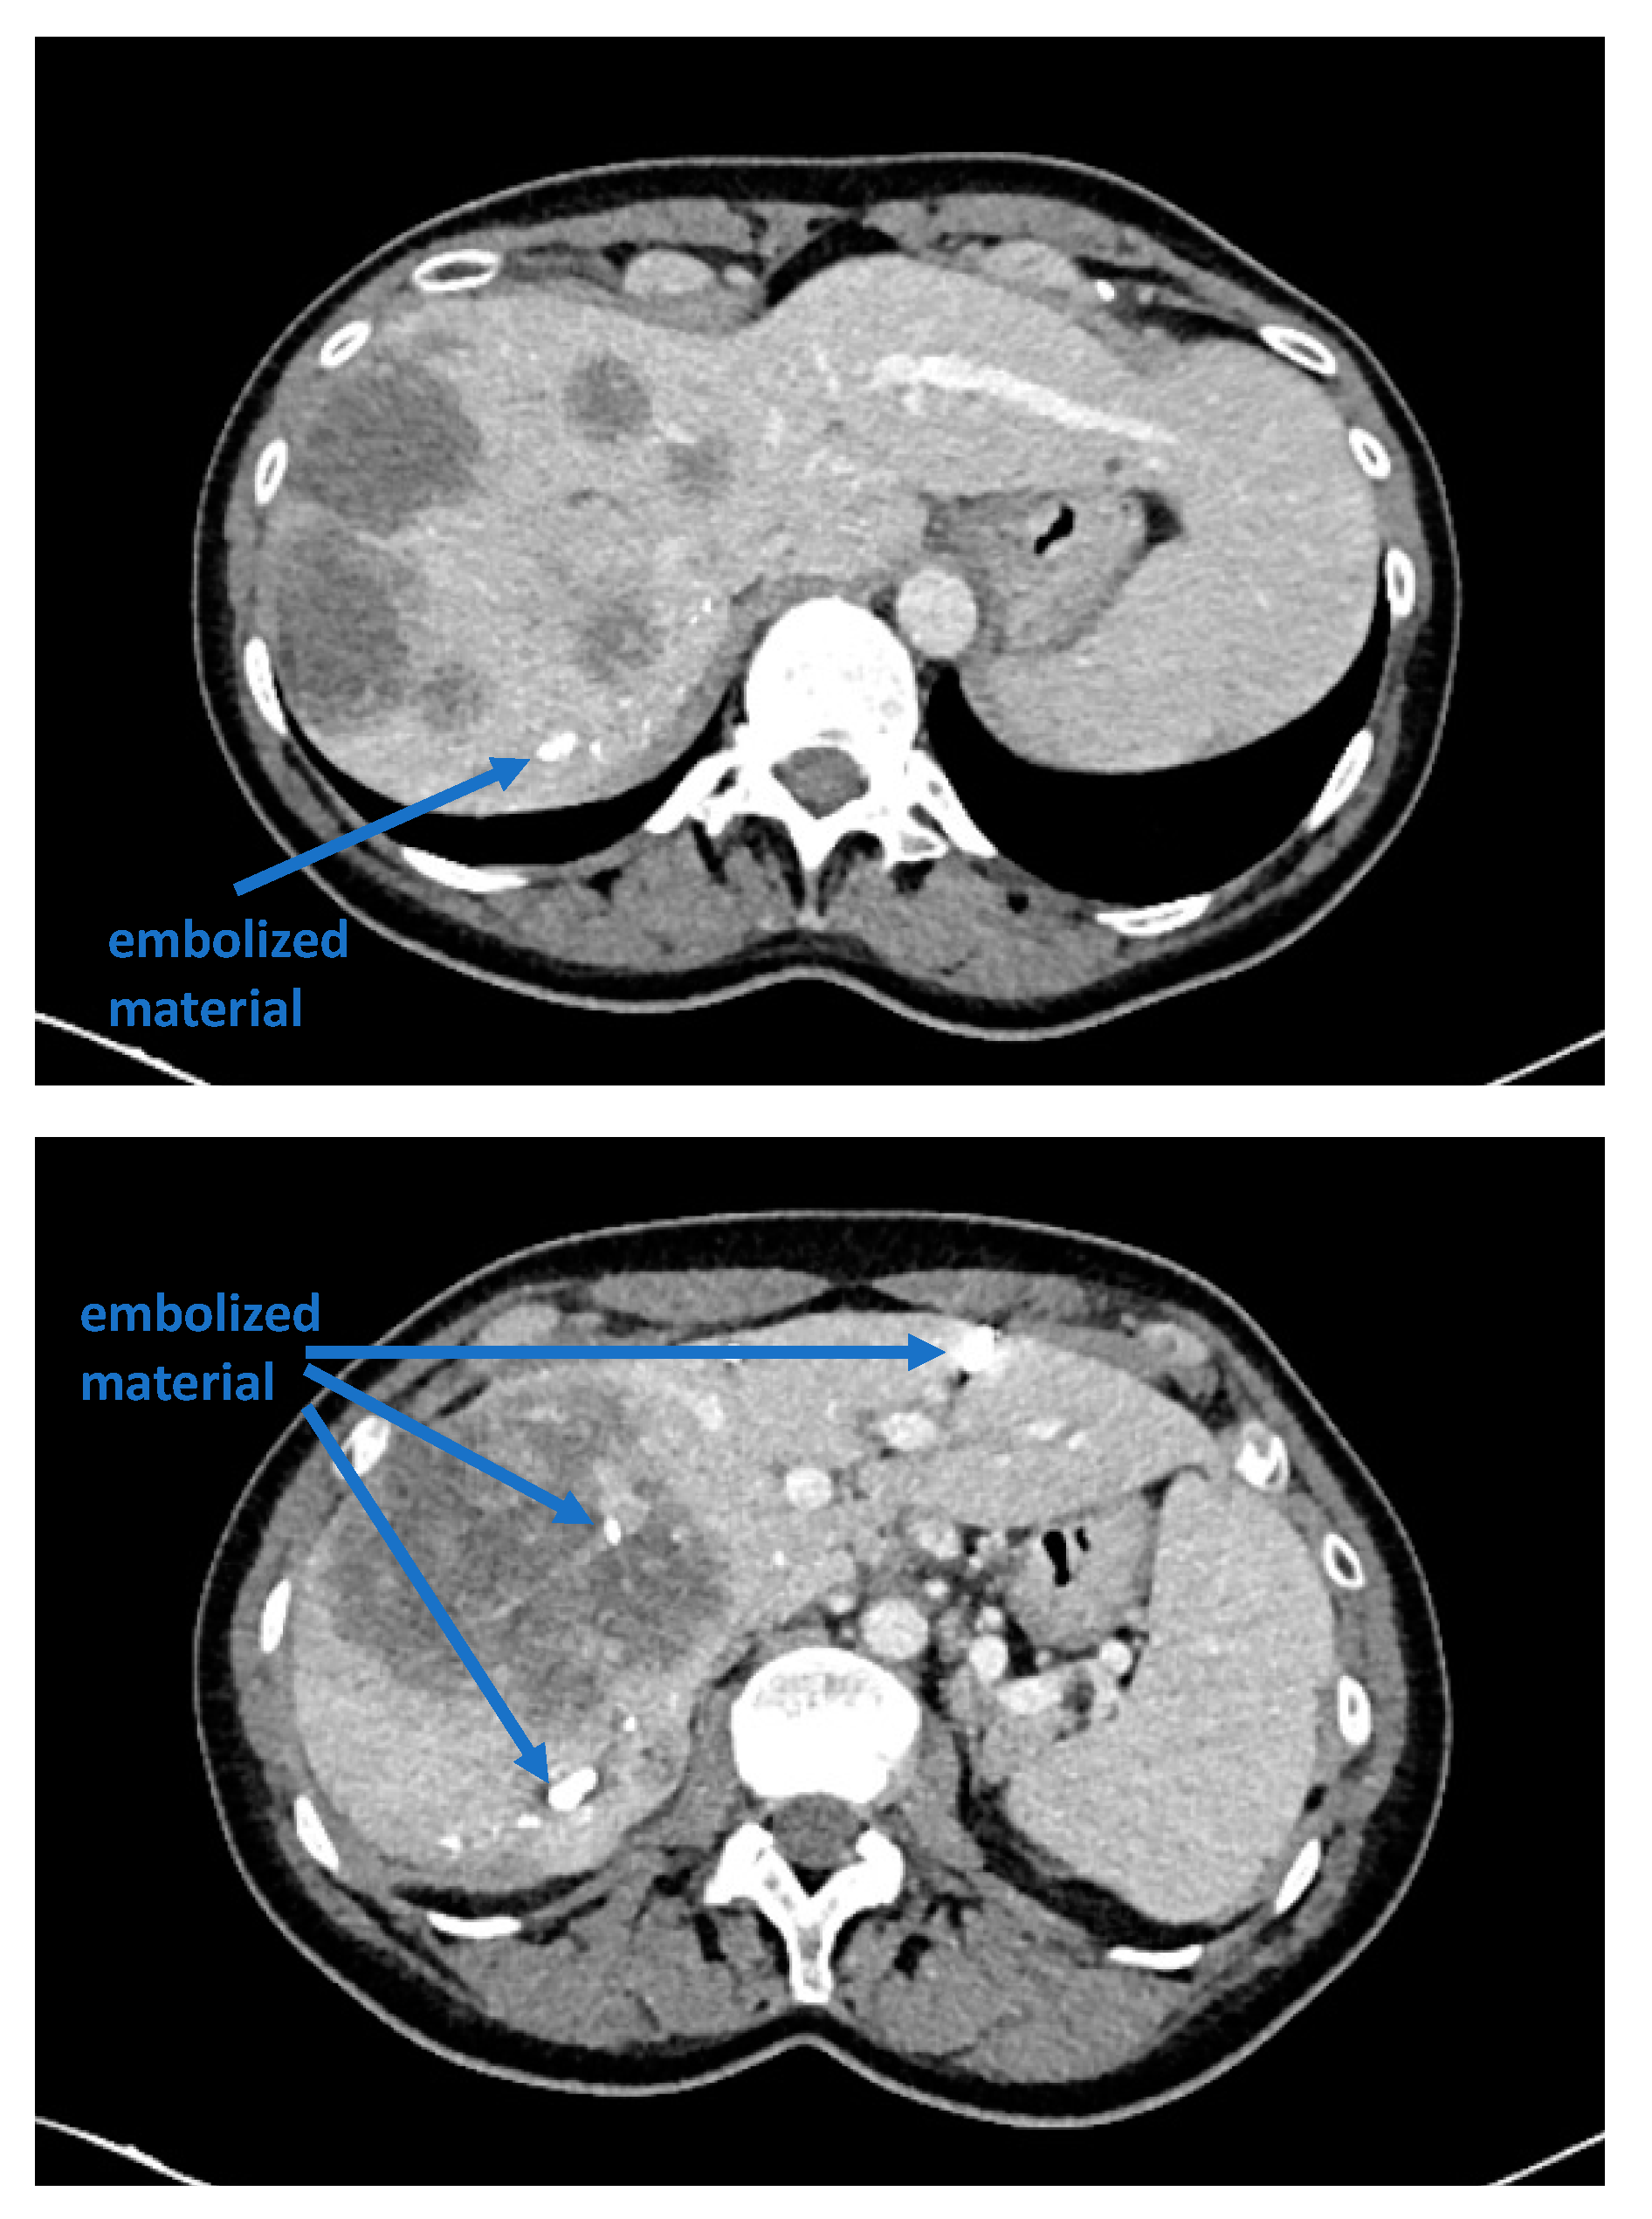

Recent reports have proposed several methods to augment the future liver remnant before extended right resection of the liver [1,2,3,4,5]. Although portal venous embolization is well established and produces satisfactory results in many patients, the growth of segments II and III is often slow and sometimes insufficient in volume (Figure 1 and Figure 2) [6,7]. This precludes many patients from potentially curative resection. The technique of in-situ liver transsection and portal venous division (also referred to as ISLT or ALPPS) and secondary completion hepatectomy, has gained some attention over the past decade to generate faster and more efficient growth of the liver remnant [3,4,5,8]. The technique of this procedure varies. Due to the high complication rate of both procedures, many modifications have been described to minimize the trauma of the first step [9,10,11]. However, a standardized initial operation can be performed safely and reduces the complication rate in the vulnerable phase before the second operation. To obtain optimal growth and to prevent situations that make the completion hepatectomy more urgent, the initial operation has to be designed to avoid bile leaks, venous congestion and segmental liver ischemia. For accurate planning of the two steps of this complex operation, a detailed understanding of the underlying pathology and the anatomy is of major importance. Preoperative imaging will have to identify arterial and venous blood supply and drainage as well as the biliary anatomy. We routinely use computed tomography with a portal and arterial phase. An MRCP is reserved for additional questions regarding the biliary tree. The patient is then presented to and discussed in our multidisciplinary hepatologic tumor board before treatment.

Figure 2. Frequently, even after careful portal venous embolization, the left lobe remains too small to enable a safe resection of the right lobe.